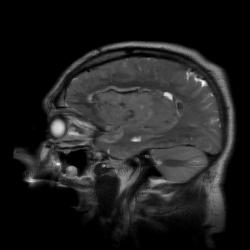

В продолжение темы нарушений мозгового кровообращения публикую случай геморрагического инсульта.

Пациент 65 лет. Заболел остро 4 часа назад. На обследование доставлен в состоянии угнетенного сознания.

Наличие крови наиболее четко видно на T2* GRE импульсной последовательности.

Наличие крови наиболее четко видно на T2* GRE импульсной последовательности.

Гематому в данном случае с головой выдает периферическая полоска, окружающая образование с гипоинтенсивным (особенно на GRE ИП) МР сигналом. Иначе чем еще ее можно объяснить?

К тому же, есть клинические данные: за 4 часа до исследования пациент на фоне головной боли внезапно потерял сознание. Привезли его уже в коме. Не мог бы человек с опухолью такого размера с височно-тенториальным вклинением и грубым вклинением под серп чувствовать себя нормально.

В данном случае это классический геморрагический инсульт. По моему опыту с таким смещением срединных структур как на представленных МР-томограммах нейрохируги редко берут на операцию - благополучный постоперационный прогноз маловероятен, да и большиноство пациентов погибают за считанные часы, многие на операционном столе. Евгений, наверное, узнает у пат.анатомов результат вскрытия и напишет нам уже верифицированный диагноз.